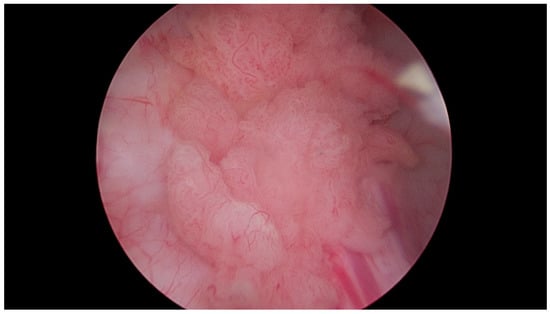

Figure 5.

Multiple papillary urothelial carcinoma of the urinary bladder—in the lower part of the image, at 8 o’clock, the vesical orifice of the right ureter is visible. Own study based on Ethical Approval of the University of Rzeszow, No. 29/05/2019. Titled 12. 2019, Evaluation of the efficacy of the in vitro photodynamic method in superficial bladder cancer, by M.D. Dominik Godlewski.